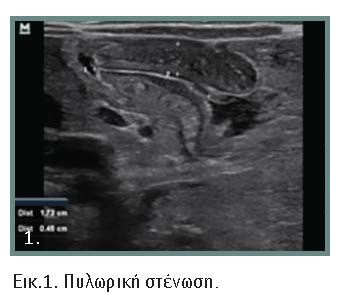

Η διάγνωση τις περισσότερες φορές είναι προφανής, όμως υπάρχουν άτυπες μορφές που μπορεί να προβληματίσουν τον κλινικό ιατρό (εικόνες 1, 2, 3, 4). Αλυσιδωτές επιπτώσεις στον οργανισμό συνθέτουν την κλινική εικόνα και τις επιπλοκές της νόσου. Με την εξέλιξη της κλινικής εικόνας και όσο δεν αντιμετωπίζεται η απόφραξη, μπορεί να εμφανιστούν βαρύτατες οξεοβασικές και ηλεκτρολυτικές διαταραχές. Οι διεγχειρητικές επιπλοκές πρέπει να αναγνωρίζονται και να αντιμετωπίζονται αμέσως γιατί οι επιπτώσεις είναι μοιραίες.